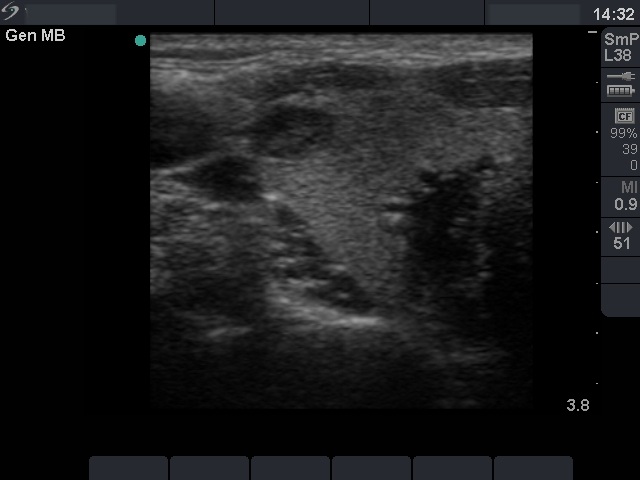

Ultrasonography: the basic echo structure of the thyroid was normal. There were three lesions in the right, and one lesion in the left lobe. The hypoechogenic one in the upper pole of the right lobe was aspirated.